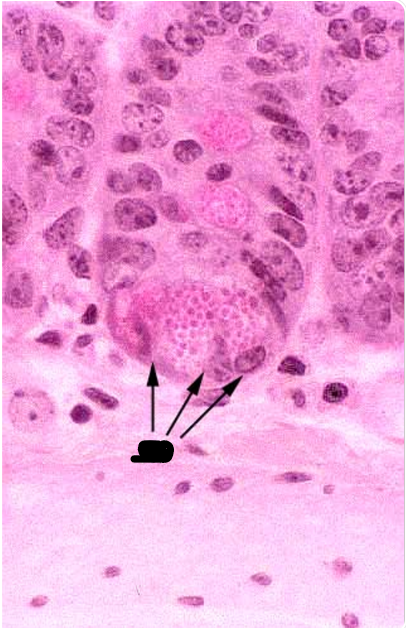

the arrows point to

Paneth cell

Auerbach’s plexus

the arrow points to

GC

ganglionic cells